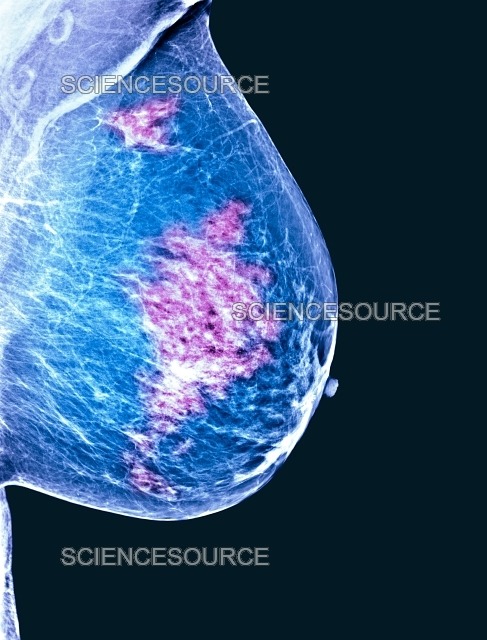

يُعدّ تصوير الثدي بالأشعة السينية الطريقة الأكثر شيوعًا للكشف عن سرطان الثدي وتشخيصه.

تشمل النتائج غير الطبيعية وجود كتل أو تكلسات أو تشوهات في بنية الثدي.

عند اكتشاف هذه التشوهات يُنصح بإجراء تصوير تشخيصي، والذي يستخدم صورًا عالية الجودة من زوايا متعددة.

كما يمكن استخدام الموجات فوق الصوتية للثدي أو التصوير بالرنين المغناطيسي (MRI) مع حقن مادة التباين.

على الرغم من أن التصوير بالرنين المغناطيسي هو أكثر فحوصات التصوير حساسية، إلا أنه يستغرق وقتًا طويلاً، ومحدود التوفر، ومكلف.